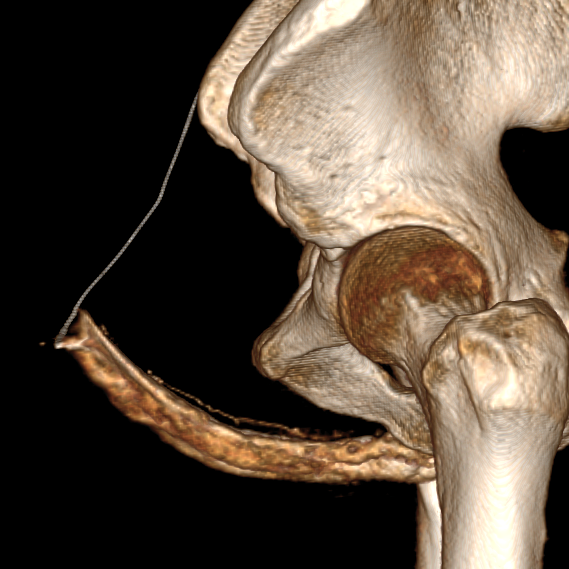

3. При венозной утечке уролог может отправить вас на абсолютно демоническую методику (которой в целом я и занималась) — КТ-кавернозографию. Однако, именно этот метод демонстрирует нам куда что утекает, и с какими сосудами будет работать сосудистый хирург. Хирург эмболизирует те сосуды, в которые происходит венозная утечка, таким образом на длительной время (пока не развились новые венозные коллатерали) обеспечит поддержание эрекции.